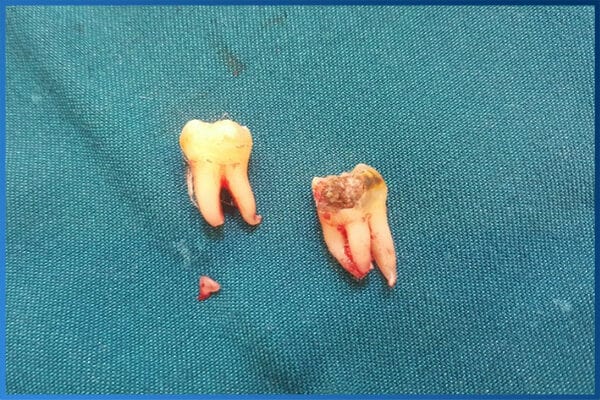

Cần phải nhổ khi chính bản thân chiếc răng khôn đó bị sâu răng hay nha chu răng.

Hình ảnh răng khôn bị sâu